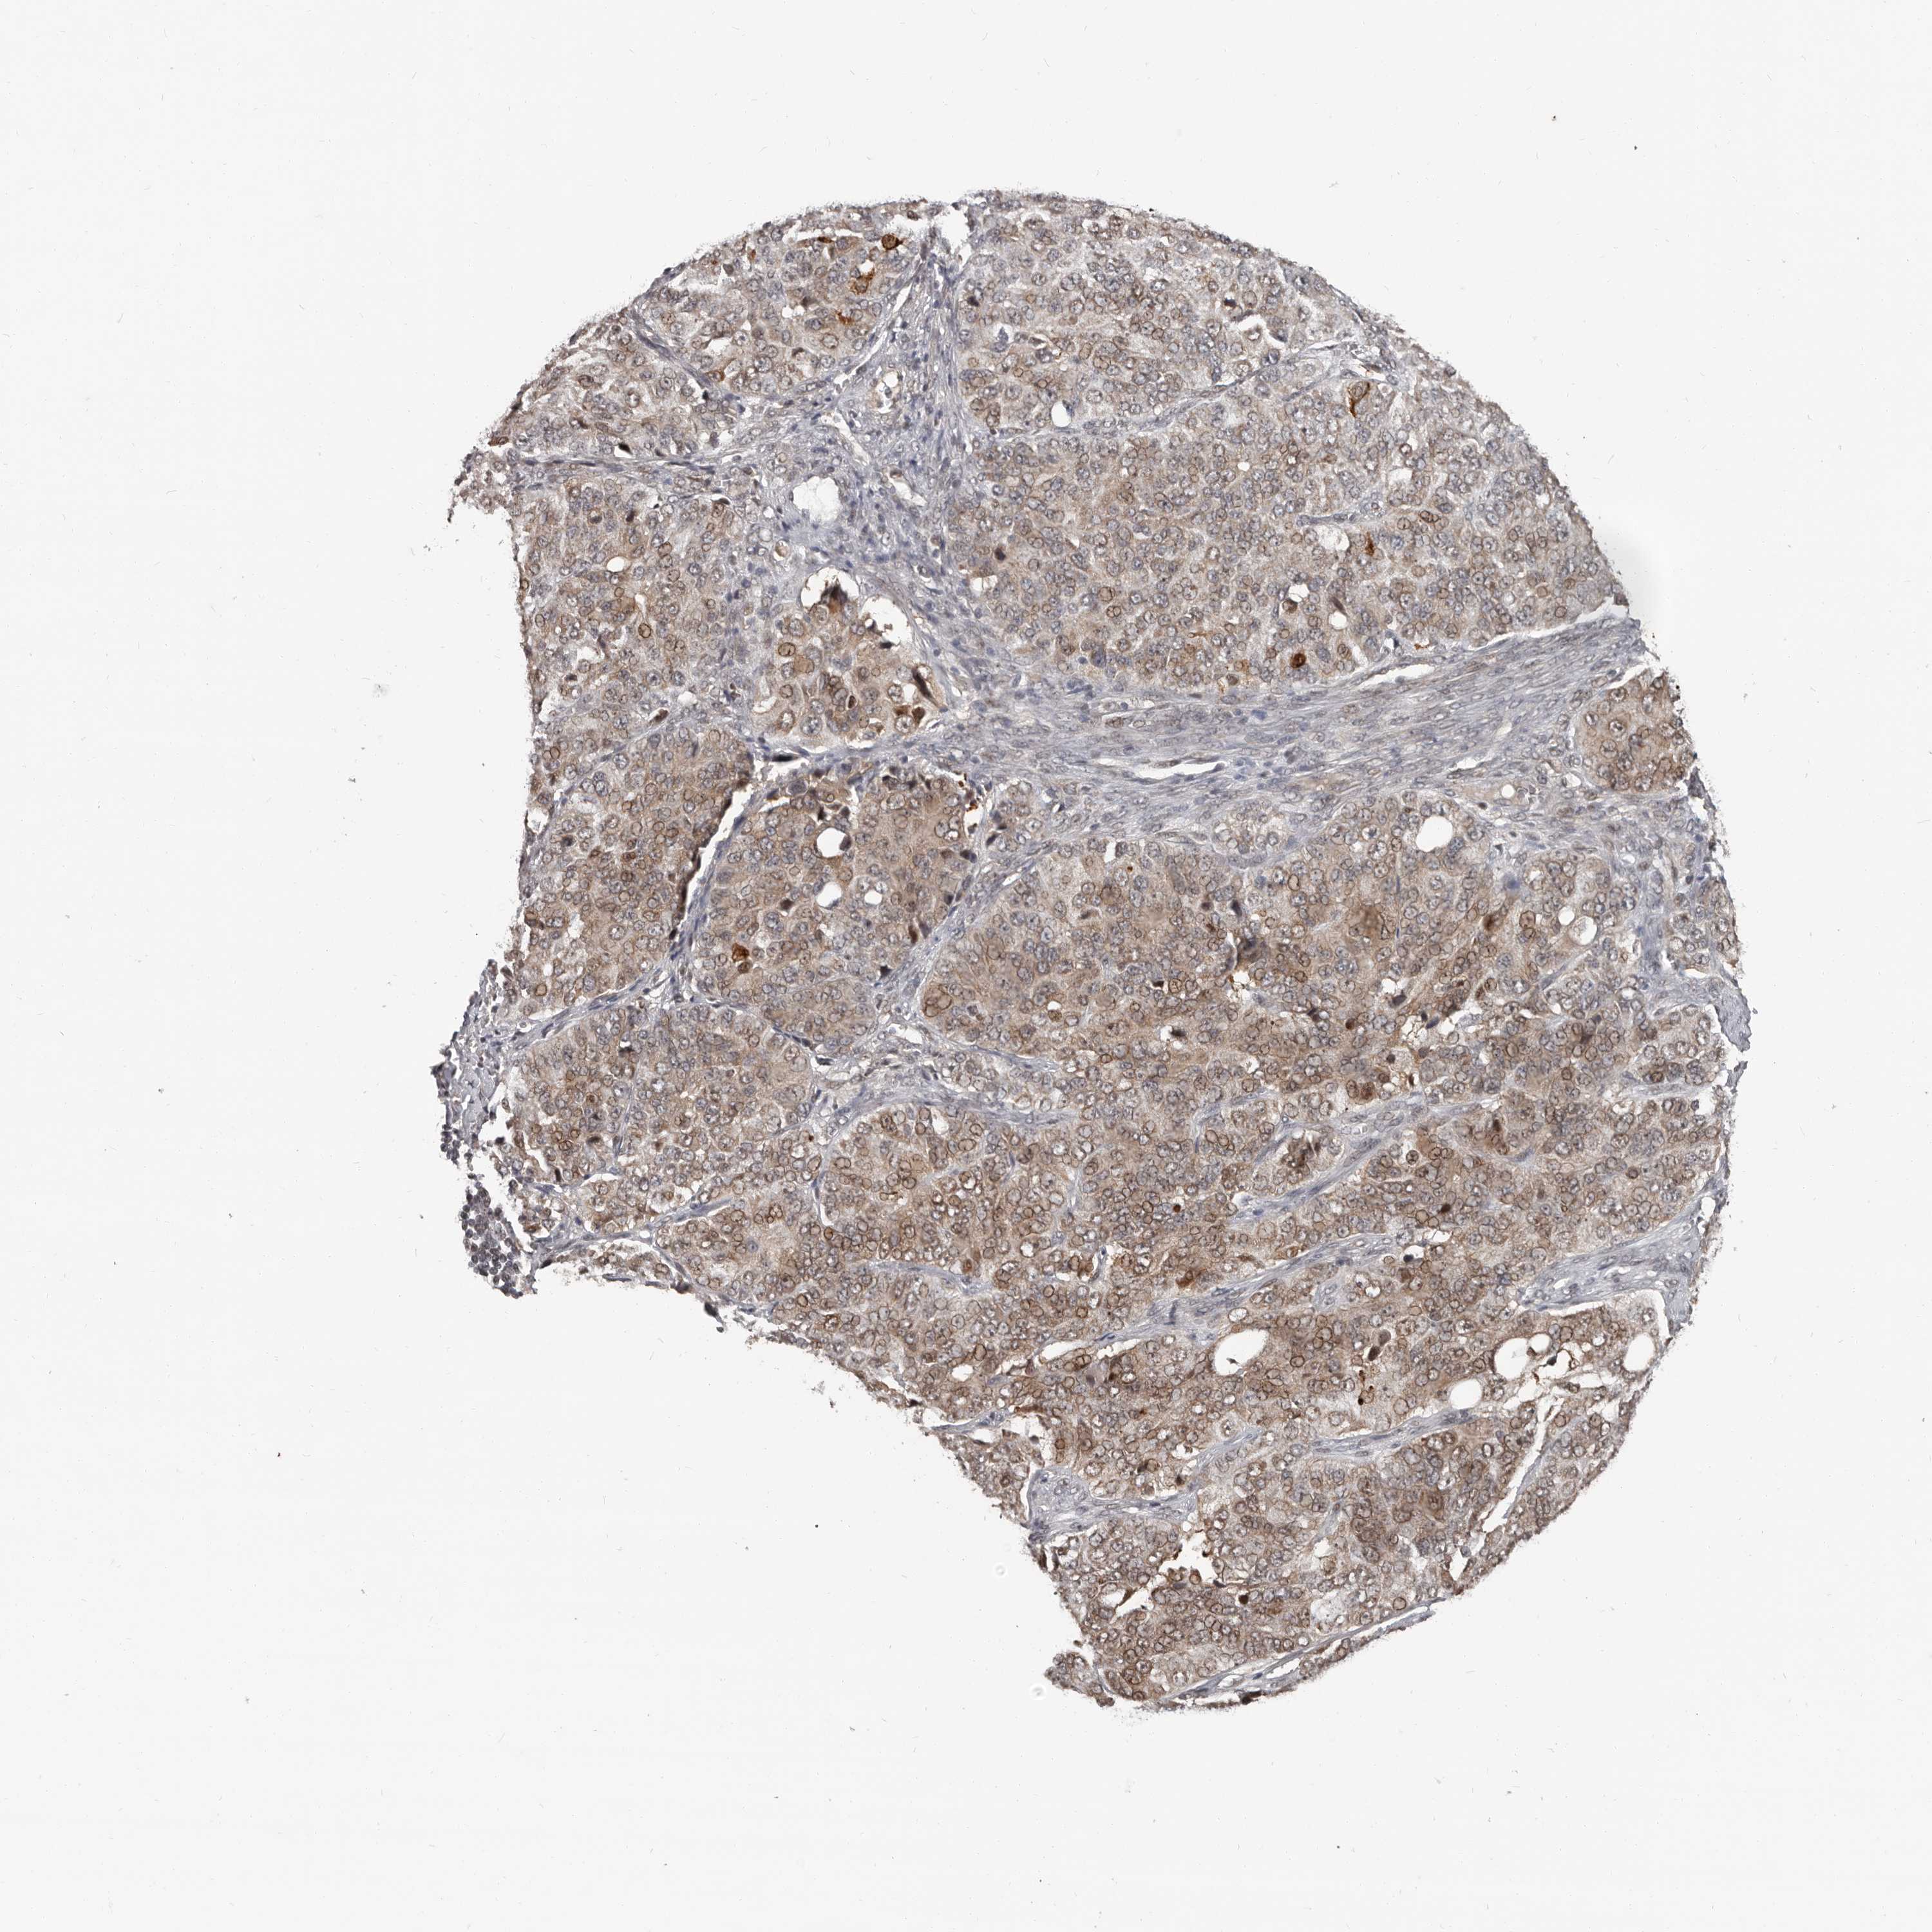

OVARIAN CANCER - Protein expressioni

A mouse-over function shows sample information and annotation data. Click on an image to view it in a full screen mode. Samples can be filtered based on level of antibody staining by selecting one or several of the following categories: high, medium, low and not detected. The assay and annotation is described here.

Note that samples used for immunohistochemistry by the Human Protein Atlas do not correspond to samples in the TCGA dataset.

Antibody stainingi

Antibody staining in the annotated cell types in the current human tissue is reported as not detected, low, medium, or high, based on conventional immunohistochemistry profiling in selected tissues. This score is based on the combination of the staining intensity and fraction of stained cells.

Each image is clickable and will lead to virtual microscopy that enables deeper exploration of all samples and also displays staining intensity scores, fraction scores and subcellular localization as well as patient and tissue information for each sample.

Antibody HPA029165

Antibody HPA029167

Antibody CAB028574

Carcinoma, endometroid